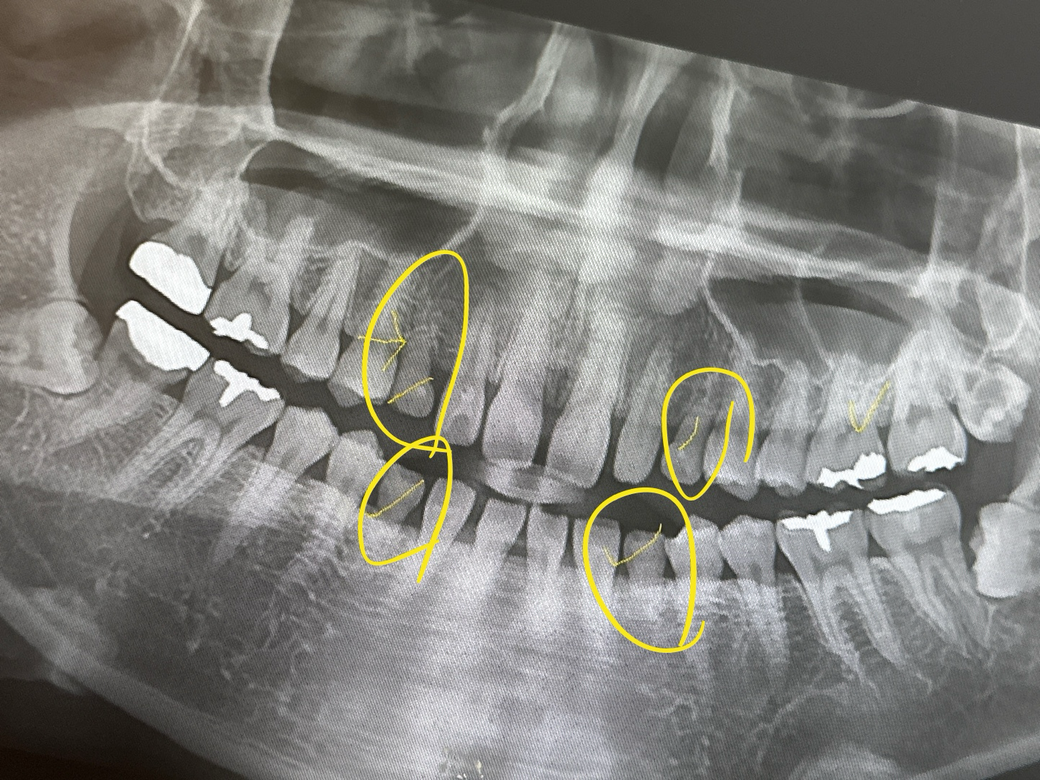

이게 현재 구강상태구요.

1. 송곳니는 영구치 결손, 유치 잔존 상태가 맞습니다.

그런데 환자분의 경우 영구치 송곳니가 결손으로 유견치가 잔존하고 있어서 유견치를 4개 발치 하시고 그 공간을 이용해 앞니를 뒤로 보내면 입술의 돌출도도 개선될 것 같습니다.

정상적으로 치아가 다 있는 경우라도 돌출 입술을 안으로 들어가게 하기 위해서는 보통 송곳니 다음의 작은 어금니를 뽑아서 그 공간으로 앞니를 넣게 됩니다.